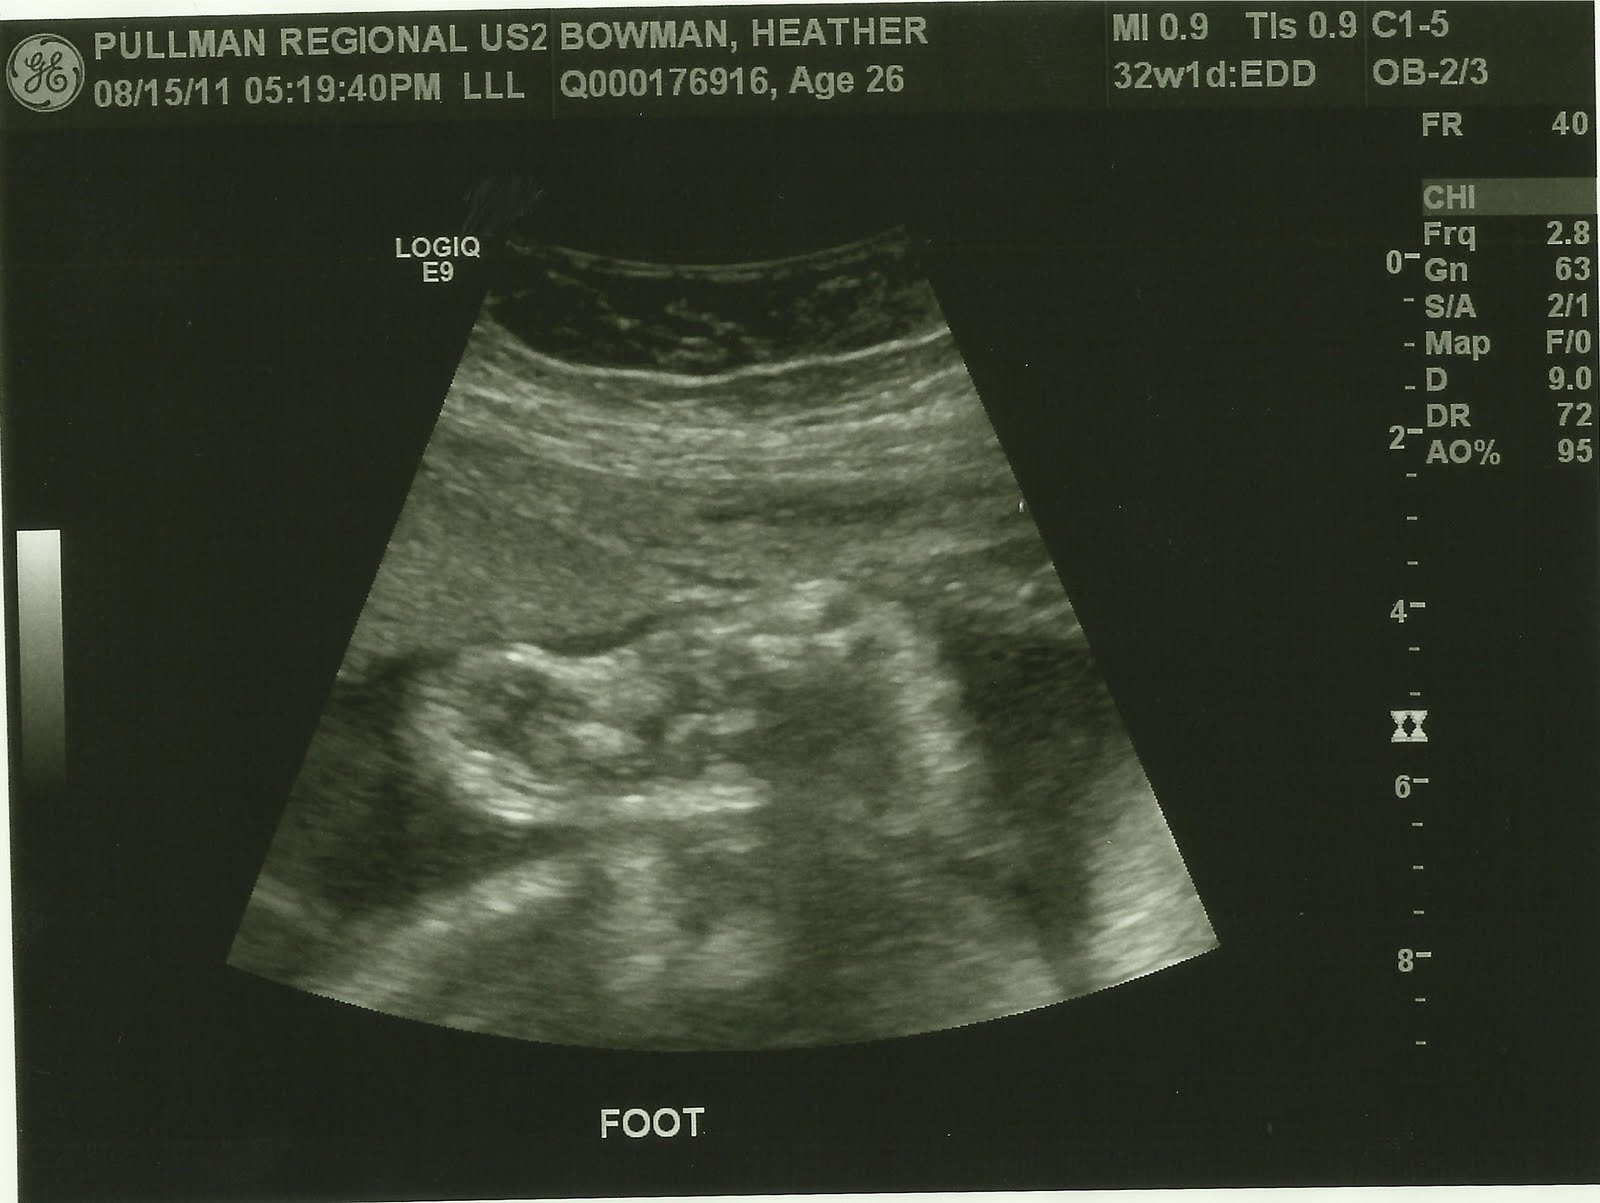

During week 33 the baby is about the size of a pineapple! It is almost 18 inches long and weighs about 5 pounds! He's getting nice and big! So far he is right on track and healthy! :) Which is always great news, especially for a diabetic!